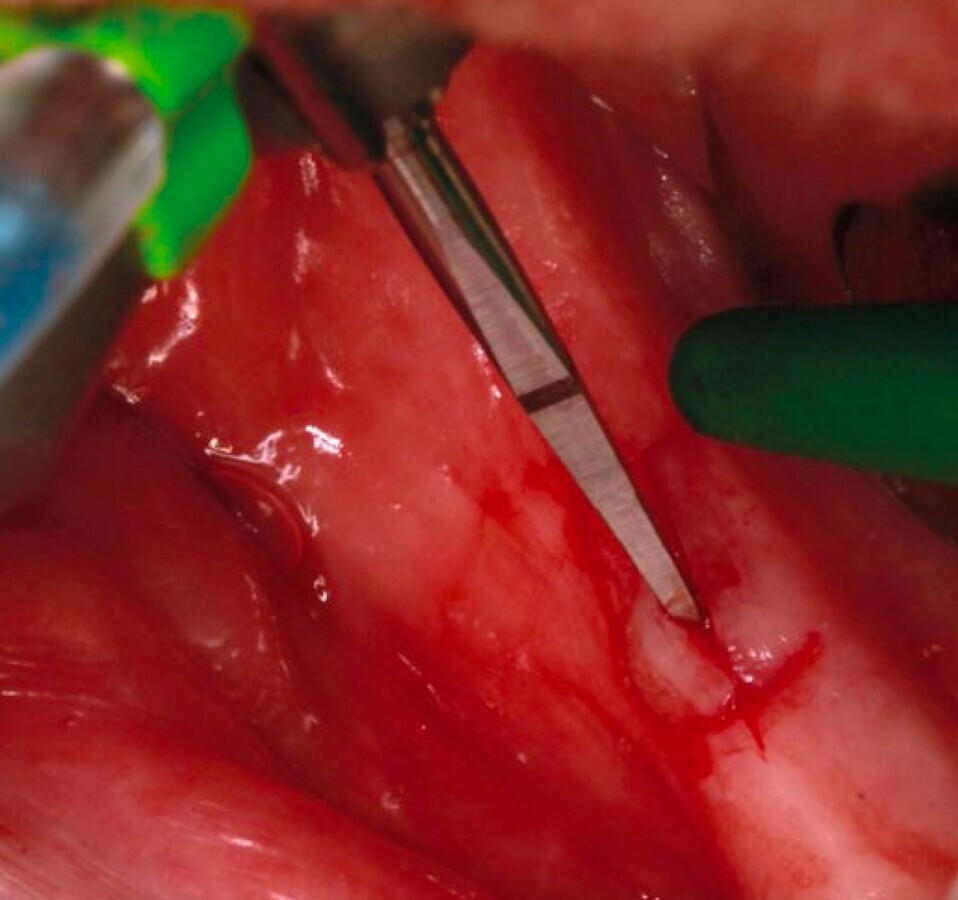

Figura 5. Incisión mínima para la colocación de un implante distal en un All-On-Four mandibular.